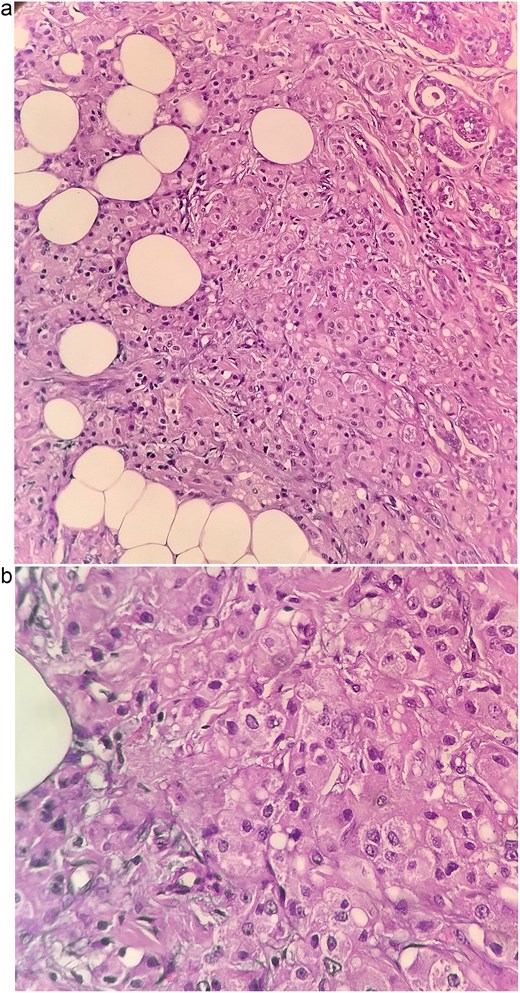

The patient underwent left breast conserving surgery with oncoplastic volume displacement and sentinel lymph node biopsy; five sentinel nodes were retrieved and all were negative intraoperatively and on final histology. Final histopathology demonstrated a 1.7 × 1 × 1 cm invasive carcinoma composed predominantly of large eosinophilic cells with vesicular nuclei, and focal low grade DCIS of cribriform and solid pattern (Fig. 3a and b). Margins were negative. The tumor was reported as carcinoma NST with apocrine differentiation, modified Bloom Richardson grade 2 (score 6). Immunohistochemistry showed ER, PR, and HER2 negativity, strong AR expression in 90% of tumor cells, Ki-67 8%, AE1/AE3, and CK7 positivity, TRPS1 focal positivity, and GATA3, DOG1 and SOX10 negativity.

Histopathological sections of the breast lesion showing characteristic apocrine morphology. (a) H&E × 100: Tumor nests composed of large polygonal cells with abundant eosinophilic granular cytoplasm and prominent nucleoli infiltrating fibroadipose tissue. (b) H&E × 400: High power view highlighting the classic apocrine cytology with vesicular nuclei, prominent nucleoli, and abundant eosinophilic cytoplasm. These features are consistent with invasive apocrine carcinoma of the breast.